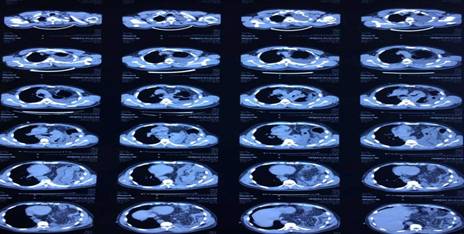

El resultado anterior se ratificó mediante la tomografía axial computarizada simple (Fig. 2) y contrastada de tórax (Fig. 3).

En este paciente los resultados de los estudios imagenológicos fueron determinantes para establecer el diagnóstico definitivo y la causa. Resulta válido destacar que este tipo de hernia se diagnostica inicialmente por el método clínico; sin embargo, el examen de elección es la radiografía de tórax, luego se ratifica mediante la tomografía axial computarizada simple y, por último, a través de la tomografía contrastada.1,4